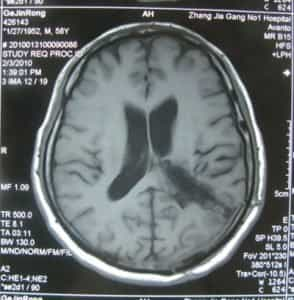

فحص بالأشعة قبل الجراحة

قبل ستة عشر شهرًا من دخوله المستشفى بسبب ورم سحائي غير نمطي في المنطقة المثلثية اليسرى، بدأ السيد جي يشعر بضعف في مرونة ساقه اليمنى، وكأنه يعاني من ضعف في حركتها. لم يسعَ للعلاج فورًا. مرت ستة أشهر، وتفاقمت الأعراض تدريجيًا، مما أثر على مشيته، وكان لصعوبة تحريك ساقه اليمنى أثر سلبي واضح على حياته. ذهب إلى مستشفى محلي وأجرى تصويرًا بالرنين المغناطيسي للدماغ، والذي أظهر وجود ورم في المنطقة المثلثية من البطين الجانبي الأيسر. نُصِحَ بالتدخل الجراحي. رغبةً منه في الخضوع لجراحة الأعصاب لعلاج هذا الورم السحائي غير النمطي، تم إدخال المريض جينرونغ جي إلى مستشفى بكين الدولي للأمراض النفسية.